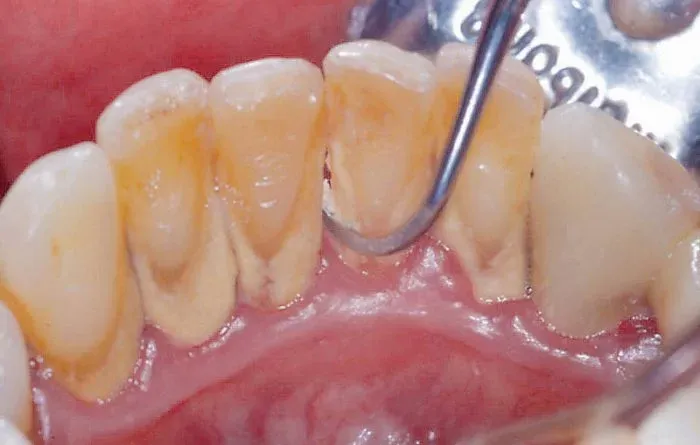

Cao răng (hay còn gọi là tartar, calculus) là những mảng bám cứng, xám hoặc vàng nâu bám chặt vào bề mặt răng, đặc biệt là gần đường viền nướu. Ban đầu, cao răng hình thành từ những mảng thức ăn thừa, vi khuẩn và khoáng chất trong nước bọt tích tụ trên răng. Nếu không được loại bỏ kịp thời bằng cách chải răng và sử dụng chỉ nha khoa thường xuyên, những mảng bám này sẽ dần bị vôi hóa, trở nên cứng và khó loại bỏ hơn rất nhiều.

• Cao răng trên nướu: Loại cao răng này thường có màu vàng hoặc cam, hình thành ở phần răng tiếp xúc với nước bọt và không khí. Cao răng trên nướu thường dễ nhìn thấy và có thể gây khó chịu khi chạm vào.

• Cao răng dưới nướu: Loại cao răng này có màu nâu sẫm hoặc đen, hình thành ở phần răng nằm dưới đường viền nướu. Cao răng dưới nướu khó phát hiện hơn và thường gây ra các vấn đề nghiêm trọng về nướu, như viêm nha chu.